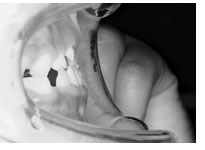

治療開始時年齢は6歳半でしたが、永久歯は1本もありませんでした。右上の乳歯Dから左上の乳歯Cまでが反対咬合の状況でした。

レントゲンの検査、家族暦などから骨格的な下顎前突の程度が大きいことがわかりましたので、オトガイ帽装置(チンキャップ)を使用することになりました。

普段のかみ合わせのまま下顎を後ろに押し下げようと力をかけた場合、上顎前歯と下顎前歯がぶつかって上顎まで後ろに下げようとする力が働いてしまいます。そこで、チンキャップを使用する場合には前歯の干渉を避けるためにクリアプレートを併用しました。

1年後(7歳半)の口腔内 下顎前歯が抜け替わりましたが、反対咬合の状態です。